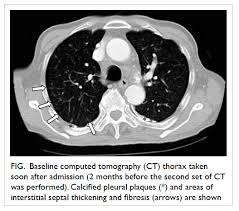

Examples Of Pleural Plaques On A A Chest Ct Arrows Indicate Pleural Download Scientific Diagram

Examples Of Pleural Plaques On A A Chest Ct Arrows Indicate Pleural Download Scientific Diagram from www.researchgate.net